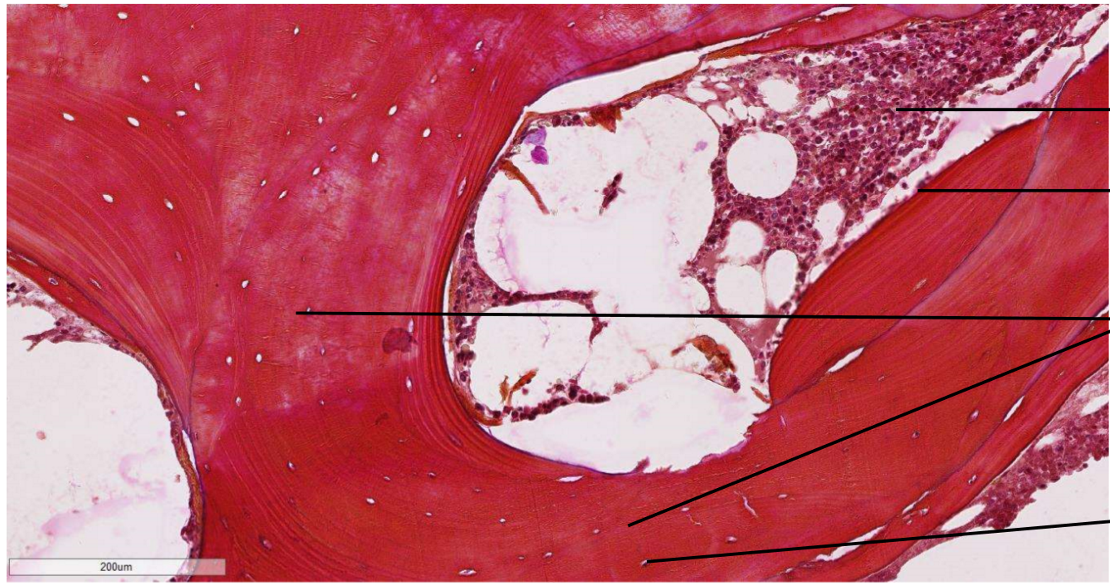

identifie la lame et les structures

lame de diaphyse décalcifiée OS COMPACT trans HPO

ostéocyte dans un ostéoplaste

ostéone (lame concentrique autour dun canal de havers)

Périoste fait de collagène

canal de havers qui comprend

1. l’endoste : ostéoblaste, cellule ostéogénique

2. VS qui contiennent globules rouges